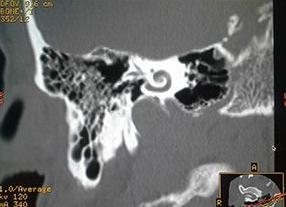

Компьютерная томограмма гипоплазии (не остаточного развития) внутреннего уха (фото: www.elsevier.es)

С помощью компьютерной томографии всегда визуализируется костный лабиринт с капсулой, внутренний слуховой проход. Определяются нарушения расположения анатомических структур, наличие объемных образований, воспалительные изменения. КТ визуализирует опухолевые новообразования: ангиомы (сосудистые опухоли), абсцессы (гнойная полость с капсулой), холестеатомы (образование круглой формы, наполненное конным салом) и невриномы.

В структуре травматологических повреждений исследование применяется для определения плоскости перелома и наличия смещения обломков. Данный тип сканирования обнаруживает любые воспалительные или инфекционные процессы, локализованные во внутреннем и среднем ухе.

Использование контрастных веществ дает возможность изучить состояние сосудов внутреннего уха. С помощью метода диагностируется врожденная и приобретенная тугоухость.